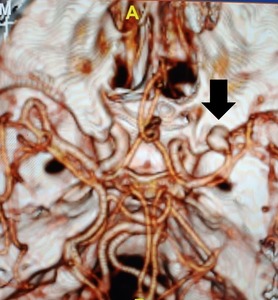

Computed tomography angiography (CTA) revealed an anomalous saccular aneurysm (7×5 mm) arising from the M1 segment of the right middle cerebral artery [Figure 2]. This finding was unusual as the branching artery demonstrated characteristics consistent with orbitofrontal artery territory supply. Digital subtraction angiography (DSA) performed via right femoral approach using a JR 3.5 5F guide catheter confirmed a Type 3 aortic arch with the anomalous aneurysm location [Figure 3]. The aneurysm demonstrated a broad neck and favorable morphology for microsurgical intervention.